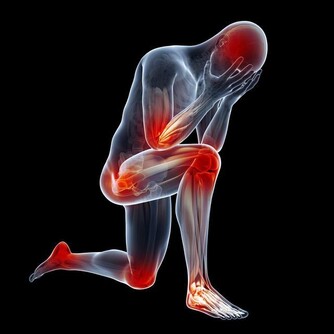

疲勞:多種類型癌症的癥狀

虛弱、乏力是多種類型癌症的癥狀。(以上皆為網絡圖片)

虛弱、乏力是多種類型癌症的癥狀,尤其是白血病。

美國癌症協會提醒,如果在睡眠充足、壓力不大的情況下,

仍然一直感覺疲憊不堪,建議儘早做個全身體檢。